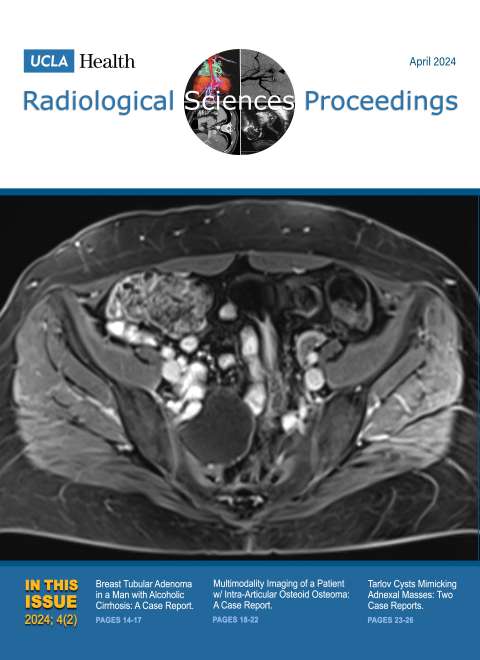

December 2024

Volume 4, Issue 4

- Smoking-Related Interstitial Lung Disease: CT Image-Based Review and Update

- Postcholecystectomy Syndrome due to Prominent Remnant of the Cystic Duct and Choledocholithiasis: A Case Report

- Kommerell Diverticulum and Agenesis of the Left Common Carotid Artery in a Patient with Dysphagia: A Case Report

- Extensive Subcutaneous Calcinosis and Hypercalcemia in the Setting of Mineral Oil-Injection-Related Foreign Body Reaction: A Case Report